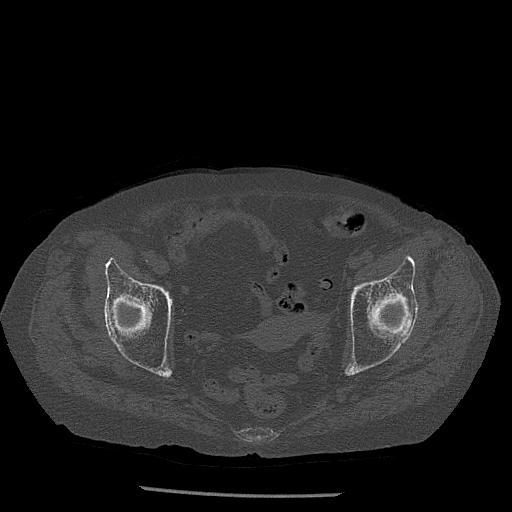

100703 1/27 両股正面+軸 1/29 両股正面+軸 94歳女性 パンソンロン

46666 1/28 両股正面+軸と 1/26 右手関節 2R 76歳女性 右転子部骨折

37 1/18 両股正面+軸 1/22 2R 86歳女性 右転子下

82084 1/14 1/20 股関節 2R 78歳男性 右人工骨頭

102811 1/13 股関節 2R 1/19 2R 80歳女性 右DHS

91569 3/25 両股正面とラウエン 70歳女性 人工骨頭+バンクーバー